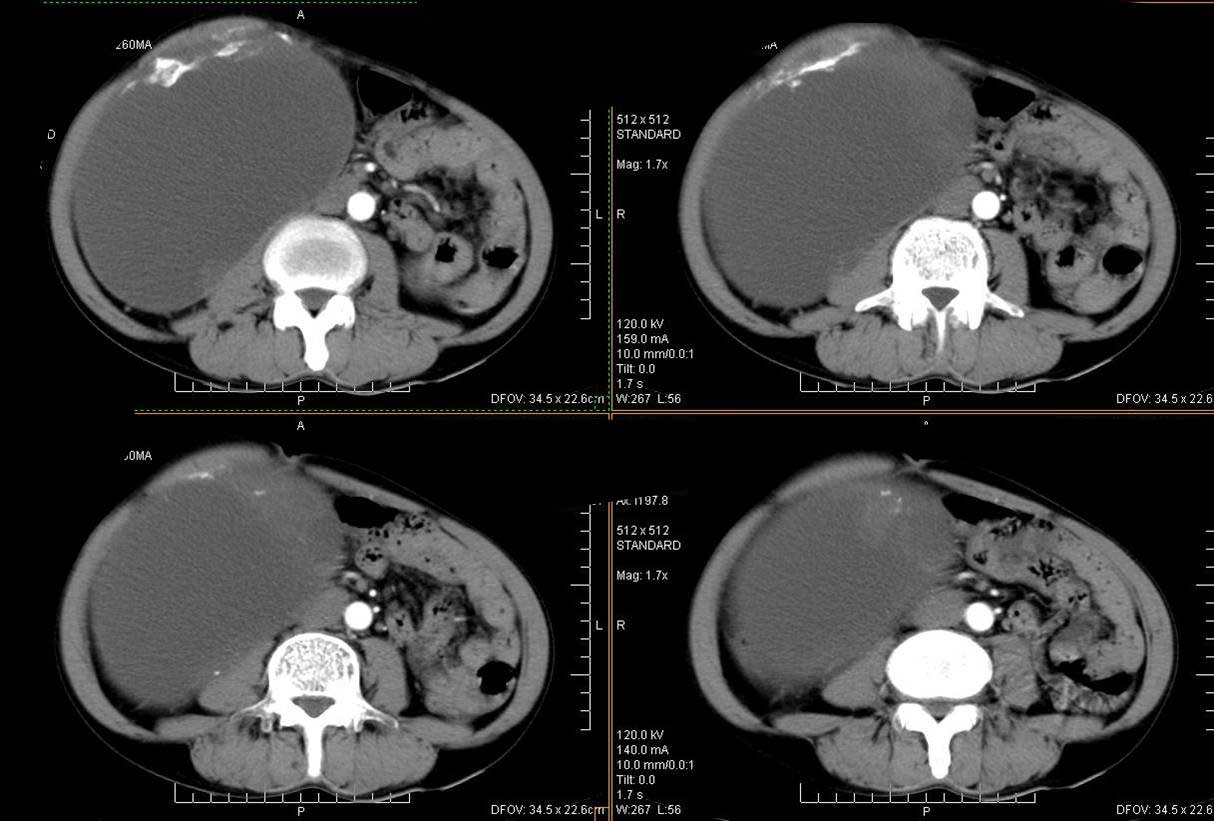

右肾脏巨大囊样影、囊壁有钙化,囊样影轻度强化有软组织成份。不除外畸胎瘤可能。

囊性肾癌可能性大,右肾多发囊肿。

巨大囊性肿块,囊壁较厚有强化,有团片状钙化,病灶内下方灶内见片絮状高密度影,增强有轻中度强化,考虑囊性肾癌可能性大

右肾上部巨大的囊实性影,实性部分轻度强化。壁有钙化。考虑右肾囊腺癌。右肾盂积水。

可考虑 1畸胎瘤 2肾包囊虫 3囊性肾瘤或囊性肾癌 4重复肾伴积水。

右侧多发性囊性病变,恶性可能性大